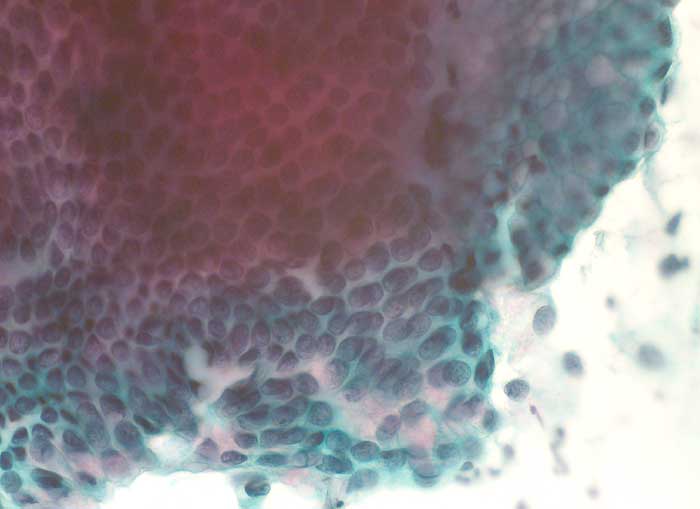

normale endozervikale Zylinderepithelien

Portioabstrich: Normale endozervikale Zylinderzellen von seitlich aufgenommen mit intrazytoplasmatischer Schleimbildung und basalständigen hellen rundlichen Kernen. Von oben betrachtet sind die Zylinderzellen in regelmässigen Abständen angeordnet und die Zellgrenzen bilden ein Honigwabenmuster.

400